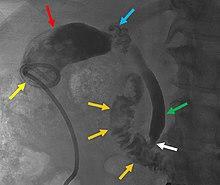

Radiography of a percutaneous drainage catheter (yellow arrow). In this control, the instilled radiocontrast is filling out the gallbladder (red arrow), where the filling defects are gallstones. The cystic duct (blue arrow) is tortuous, the common bile duct (green arrow) is mildly dilated but patent, with tapering at ampulla Vateri (white arrow), but without obstruction. Contrast was seen extending into the duodenum (orange arrows), demonstrating open passage through the bile ducts.[37]

In cases of severe inflammation, shock, or if the person has higher risk for general anesthesia (required for cholecystectomy), an interventional radiologist may insert a percutaneous drainage catheter into the gallbladder (percutaneous cholecystostomy tube) and treat the person with antibiotics until the acute inflammation resolves. A cholecystectomy may then be warranted if the person's condition improves.